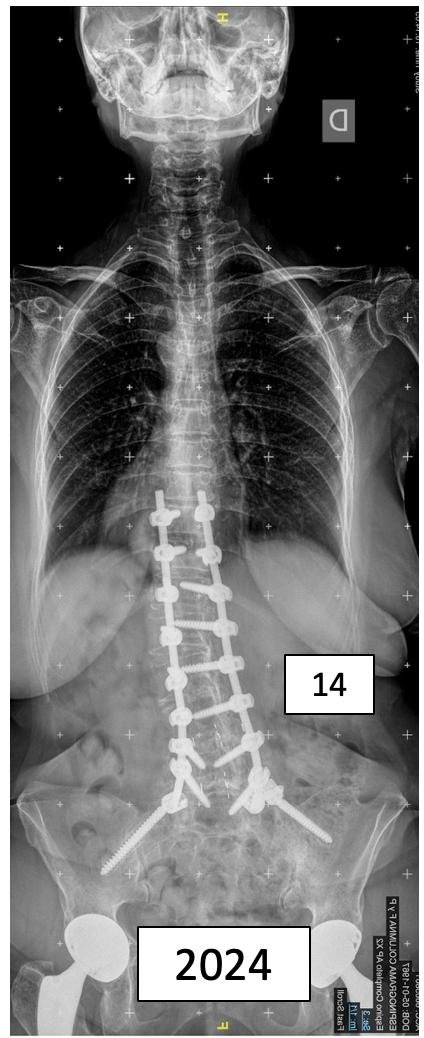

Marcela

DR. PABLO FIORILLO – Mat. 17034

Cirujano de Columna

Especialista en Escoliosis Pediatricos y Adultos